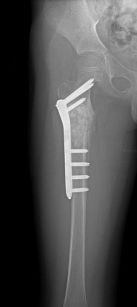

Fibröz displazinin altı aylık aralarla alınacak filmlerlekontrolu yapılır. Bifosfanatlar medikal tedavide altın standarttır. Patolojik kırık veya patolojik kırık gelişme ihtimali yüksek olduğunda kanal içi çivileme ile tedavi edilir. Deformite geliştiğinde düzeltici osteotomi ve internal osteosentez uygulanır. Cerrahi tedavide; küretaj +grefonaj, yüksek nüks nedeni ile gözardı edilir, kanal içi osteosentez uygulanır. Ayrıca deformitenin gelişmesini engellemek için de geniş lezyonlarda koruyucu internal fiksasyon da yapılır. Büyüme kıkırdaklarının aktif olduğu dönemlerde intramedüller çivileme bu bölgelere zarar verebilir. Tedavide amaç deformitelerin oluşmasını engellemek ve var olanı düzeltmektir. Monostotik formlarda %0,4 oranında kötü huylu tümöre (malignite) dönüş bildirilmiştir.